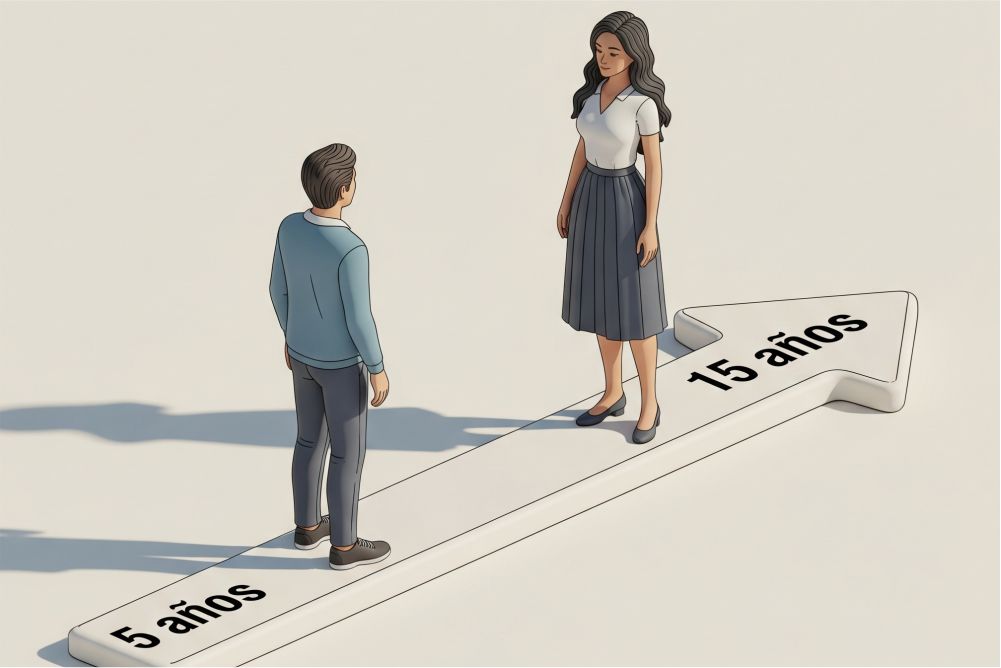

Evolución lenta

Los síntomas pueden tardar años en aparecer.